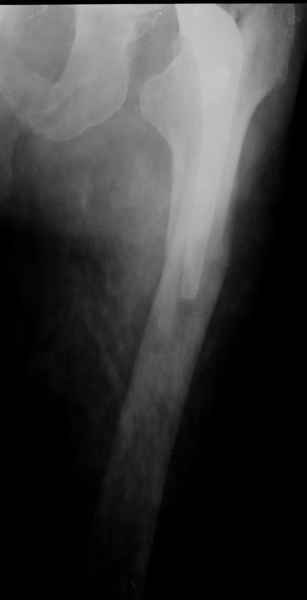

ножка просела немного (вопрос, много - это сколько?)перечисленные проблемы - не самое важное сейчас, на них можно закрыть глаза. Ножка явно нестабильна, проксимальный отломок с б/вертелом к гвоздю не прицепить, срастется ли он с ножкой

Можно уверенно рассчитывать на сращение фрагментов бедра между собой. Можно ли рассчитывать на реинтеграцию имеющейся ножки в проксимальном отделе - действительно вопрос открытый. Но во всяком случае ножка будет заметное время стабильной за счет дистальной фиксации. Будет ли это время достаточно на всю оставшуюся жизнь пациента - трудно предугадать.

Но, как Александр Виноградский справедливо заметил, после сращения бедра появляется возможность поставить даже обычную ножку большего размера.